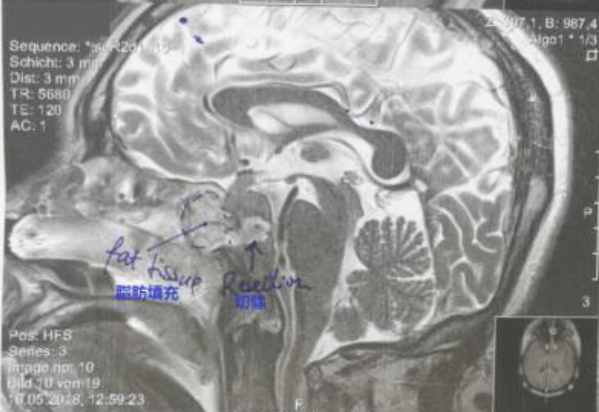

术后第2天,李先生出ICU,被转入普通病房。主刀巴特朗菲教授来查房,告知手术很成功,同时解释了切除率以及术中所见及下一步的安排等问题,同时告知初步活检结果为鼻咽癌WHO 3 型。残留的一点肿瘤主要是包裹着大动脉,为了保证安全,没有冒险切除,同时用脂肪做了一些填充。